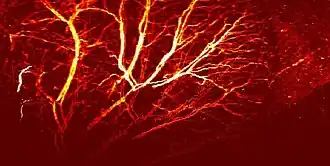

Visible light absorbers (λ = 400 to 700 nm) include oxyhemoglobin, deoxyhemoglobin, melanin, and cytochrome c. Visible light photoacoustic microscopy is particularly useful in determining hemoglobin concentration and oxygen saturation due to the difference in absorption profiles of oxyhemoglobin and deoxyhemoglobin. Real-time analysis can then be used to determine blood flow speed and oxygen metabolism rate.[3] In addition, photoacoustic microscopy is capable of early melanoma detection due to the high concentration of melanin found in skin cancer cells.

Photoacoustic microscopy has a wide range of applications in the biomedical field. Due to its ability to image a variety of molecules based on optical wavelength, photoacoustic microscopy can be used to gain functional information about the body noninvasively. Blood flow dynamics and oxygen metabolic rates can be measured and correlated to studies of atherosclerosis or tumor proliferation. Exogenous agents can be used to bind to cancerous tissue, enhancing image contrast and aiding in surgical removal. On the same note, photoacoustic microscopy is useful in early cancer diagnosis due to the difference in optical absorption properties compared to healthy tissue.[1]